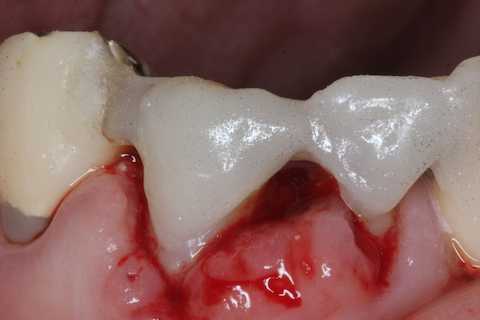

前回 ​のつづきで、再植と化粧をする。さすがに歯なしでは寂しい。

普通にズブズブと抜歯窩に再建した歯根を挿入する。

あとは接着固定しながら、歯冠を再建していく。